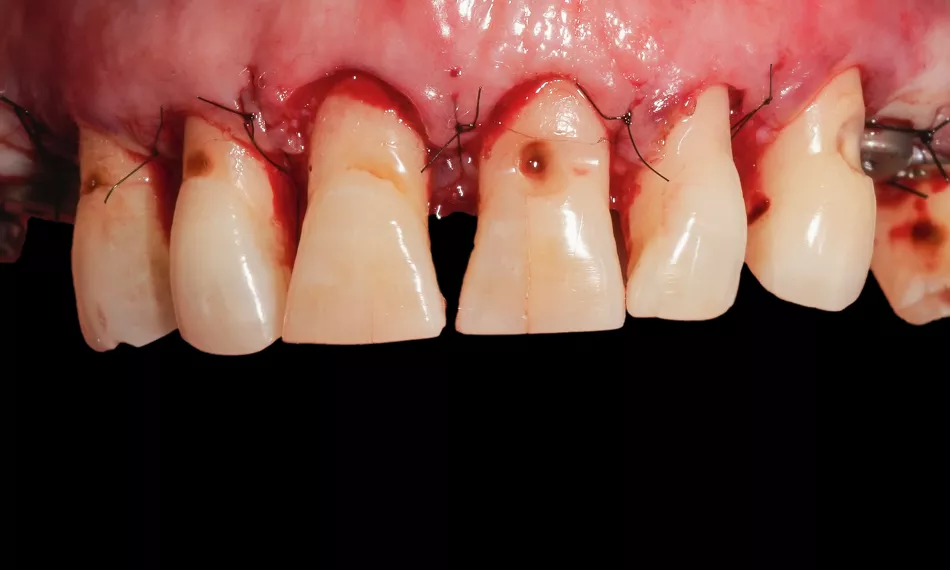

Once proper seating of the guides was confirmed, guided osteotomies were performed according to the preoperative virtual plan, using sequential drilling under copious irrigation to minimize trauma. The accuracy of guide positioning enabled precise execution of the crown lengthening procedure with controlled bone removal, ensuring ideal prosthetic space and emergence profiles. Furthermore, the implants were placed at the following sites: #14 – Straumann® BLX Ø4.0 mm, length 12 mm; #16 - Straumann® BLX Ø4.0 mm, length 8 mm; #24 – Straumann® BLX Ø3.75 mm, length 10 mm; #25 – Straumann® BLX Ø3.75 mm, length 10 mm; (Figs. 8 - 9).

Optimal contour and soft tissue adaptation were achieved, and the surgical sites were thoroughly irrigated with sterile saline to remove any bone debris. The flaps were repositioned and carefully sutured to ensure a tension-free primary closure (Fig. 10).